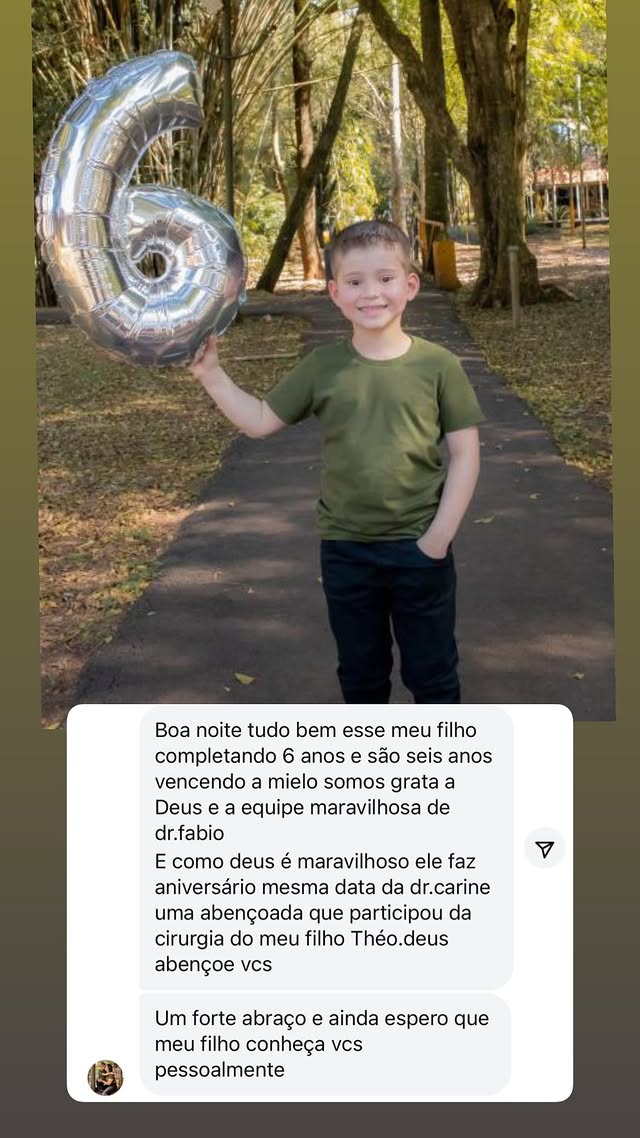

Esperança viva: descubra o futuro

que a Valentina conquistou

"Valentina é a prova de que a força nasce junto com a vida. Hoje inspira todos ao seu redor com sua coragem. Sua trajetória mostra que, com apoio, fé e amor, é possível transformar desafios em conquistas. Essa é a história de uma menina que não se limitou ao diagnóstico, mas abraçou o futuro com esperança viva."